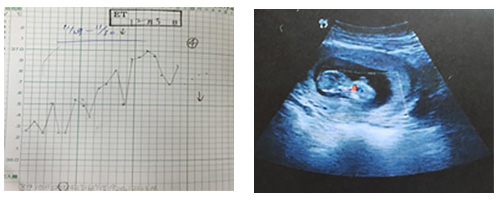

1か月後、基礎体温は2相になっていたが、ギザギザで高温期10日間程度。

2か月後、卵子の状態も改善して(腹部エコーより)、高温期は13日間。

3か月後(今月)、妊娠が確認された。

現在、漢方の保胎治療を継続中(黄体機能不全は流産のリスクが高いため)。